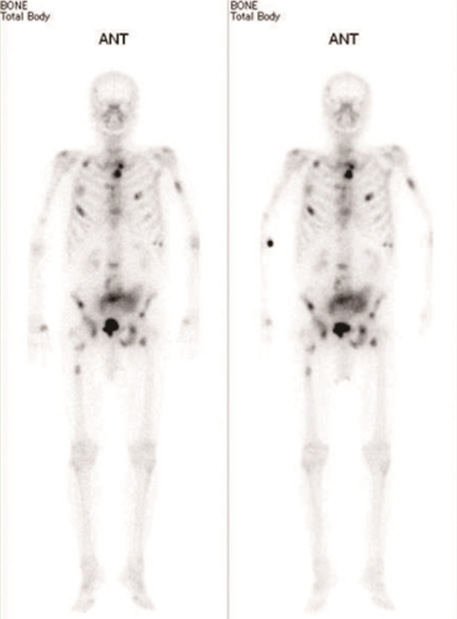

骨シンチグラフィー

目的:骨の代謝を調べる検査です。この検査により骨の代謝の異常箇所が分かります。

検査手順:検査薬を注射し2~3時間後に撮影します。撮影時間は約30分です。

画像の一例

骨の異常箇所が黒く写っています。